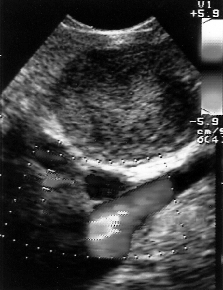

Эндосонография диагностическая методика, высокотехнологическое исследование, одновременно сочетающее в себе возможности эндоскопической и ультразвуковой диагностики.

Для исследования используют гибкий эндоскоп с видеокамерой и ультразвуковым датчиком. Его можно ввести в пищевод, желудок, двенадцатиперстную, прямую, толстую кишку, а также в дыхательные пути. Во время обычного ультразвукового исследования через кожу, когда нужно осмотреть орган, который находится глубоко, страдает четкость изображения. Эндосонография решает эту проблему. При помощи эндоскопа УЗ-датчик подводят максимально близко к исследуемому образованию. Во время исследования врач может провести тонкоигольную биопсию подозрительного образования. Использование в приборе очень высоких частот ультразвука (5,0; 7,5; 12 и 20 МГц) обеспечивает высокое качество изображения с разрешающей способностью менее 1 мм, недоступное другим методам исследования, таким как обычное ультразвуковое исследование, компьютерная и магнитно-резонансная томография, эндоскопическая холангиопанкреатикография. При этом эндосонография не сопряжена с риском рентгенологического облучения персонала и пациента, отсутствует опасность возникновения осложнений, свойственных ЭРХПГ.

Какое оборудование используется?

Существует два различных типа эхо-эндоскопов по типу сканирования ультразвуковыми датчиками:

• радиального - перпендикулярны оси эндоскопа - сканируют 360 градусов - диагностический

• конвексного - параллельно оси эндоскопа - сканируют примерно 100 градусов - имеет специальный "инструментальный" канал

Радиальное сканирование позволяет получить панорамное изображение (360°), перпендикулярное оси эндоскопа. Это наиболее ранние и самые распространенные модели эхо-эндоскопов, используются они только в диагностических целях.

Эхоэндоскопы конвексного типа сканирования введены в клиническую практику с 1990-х годов и позволяют получать 100° секторное ультразвуковое изображение, параллельное оси эндоскопа. Использование аппаратов данного типа, оснащенных инструментальным каналом, позволяет проводить пункционную биопсию под ЭСГ-контролем (ЭСГ-ПБ). Комплектация эхосканеров допплеровским и соно-эластографическими блоками значительно расширяет диагностические и лечебные возможности исследования.